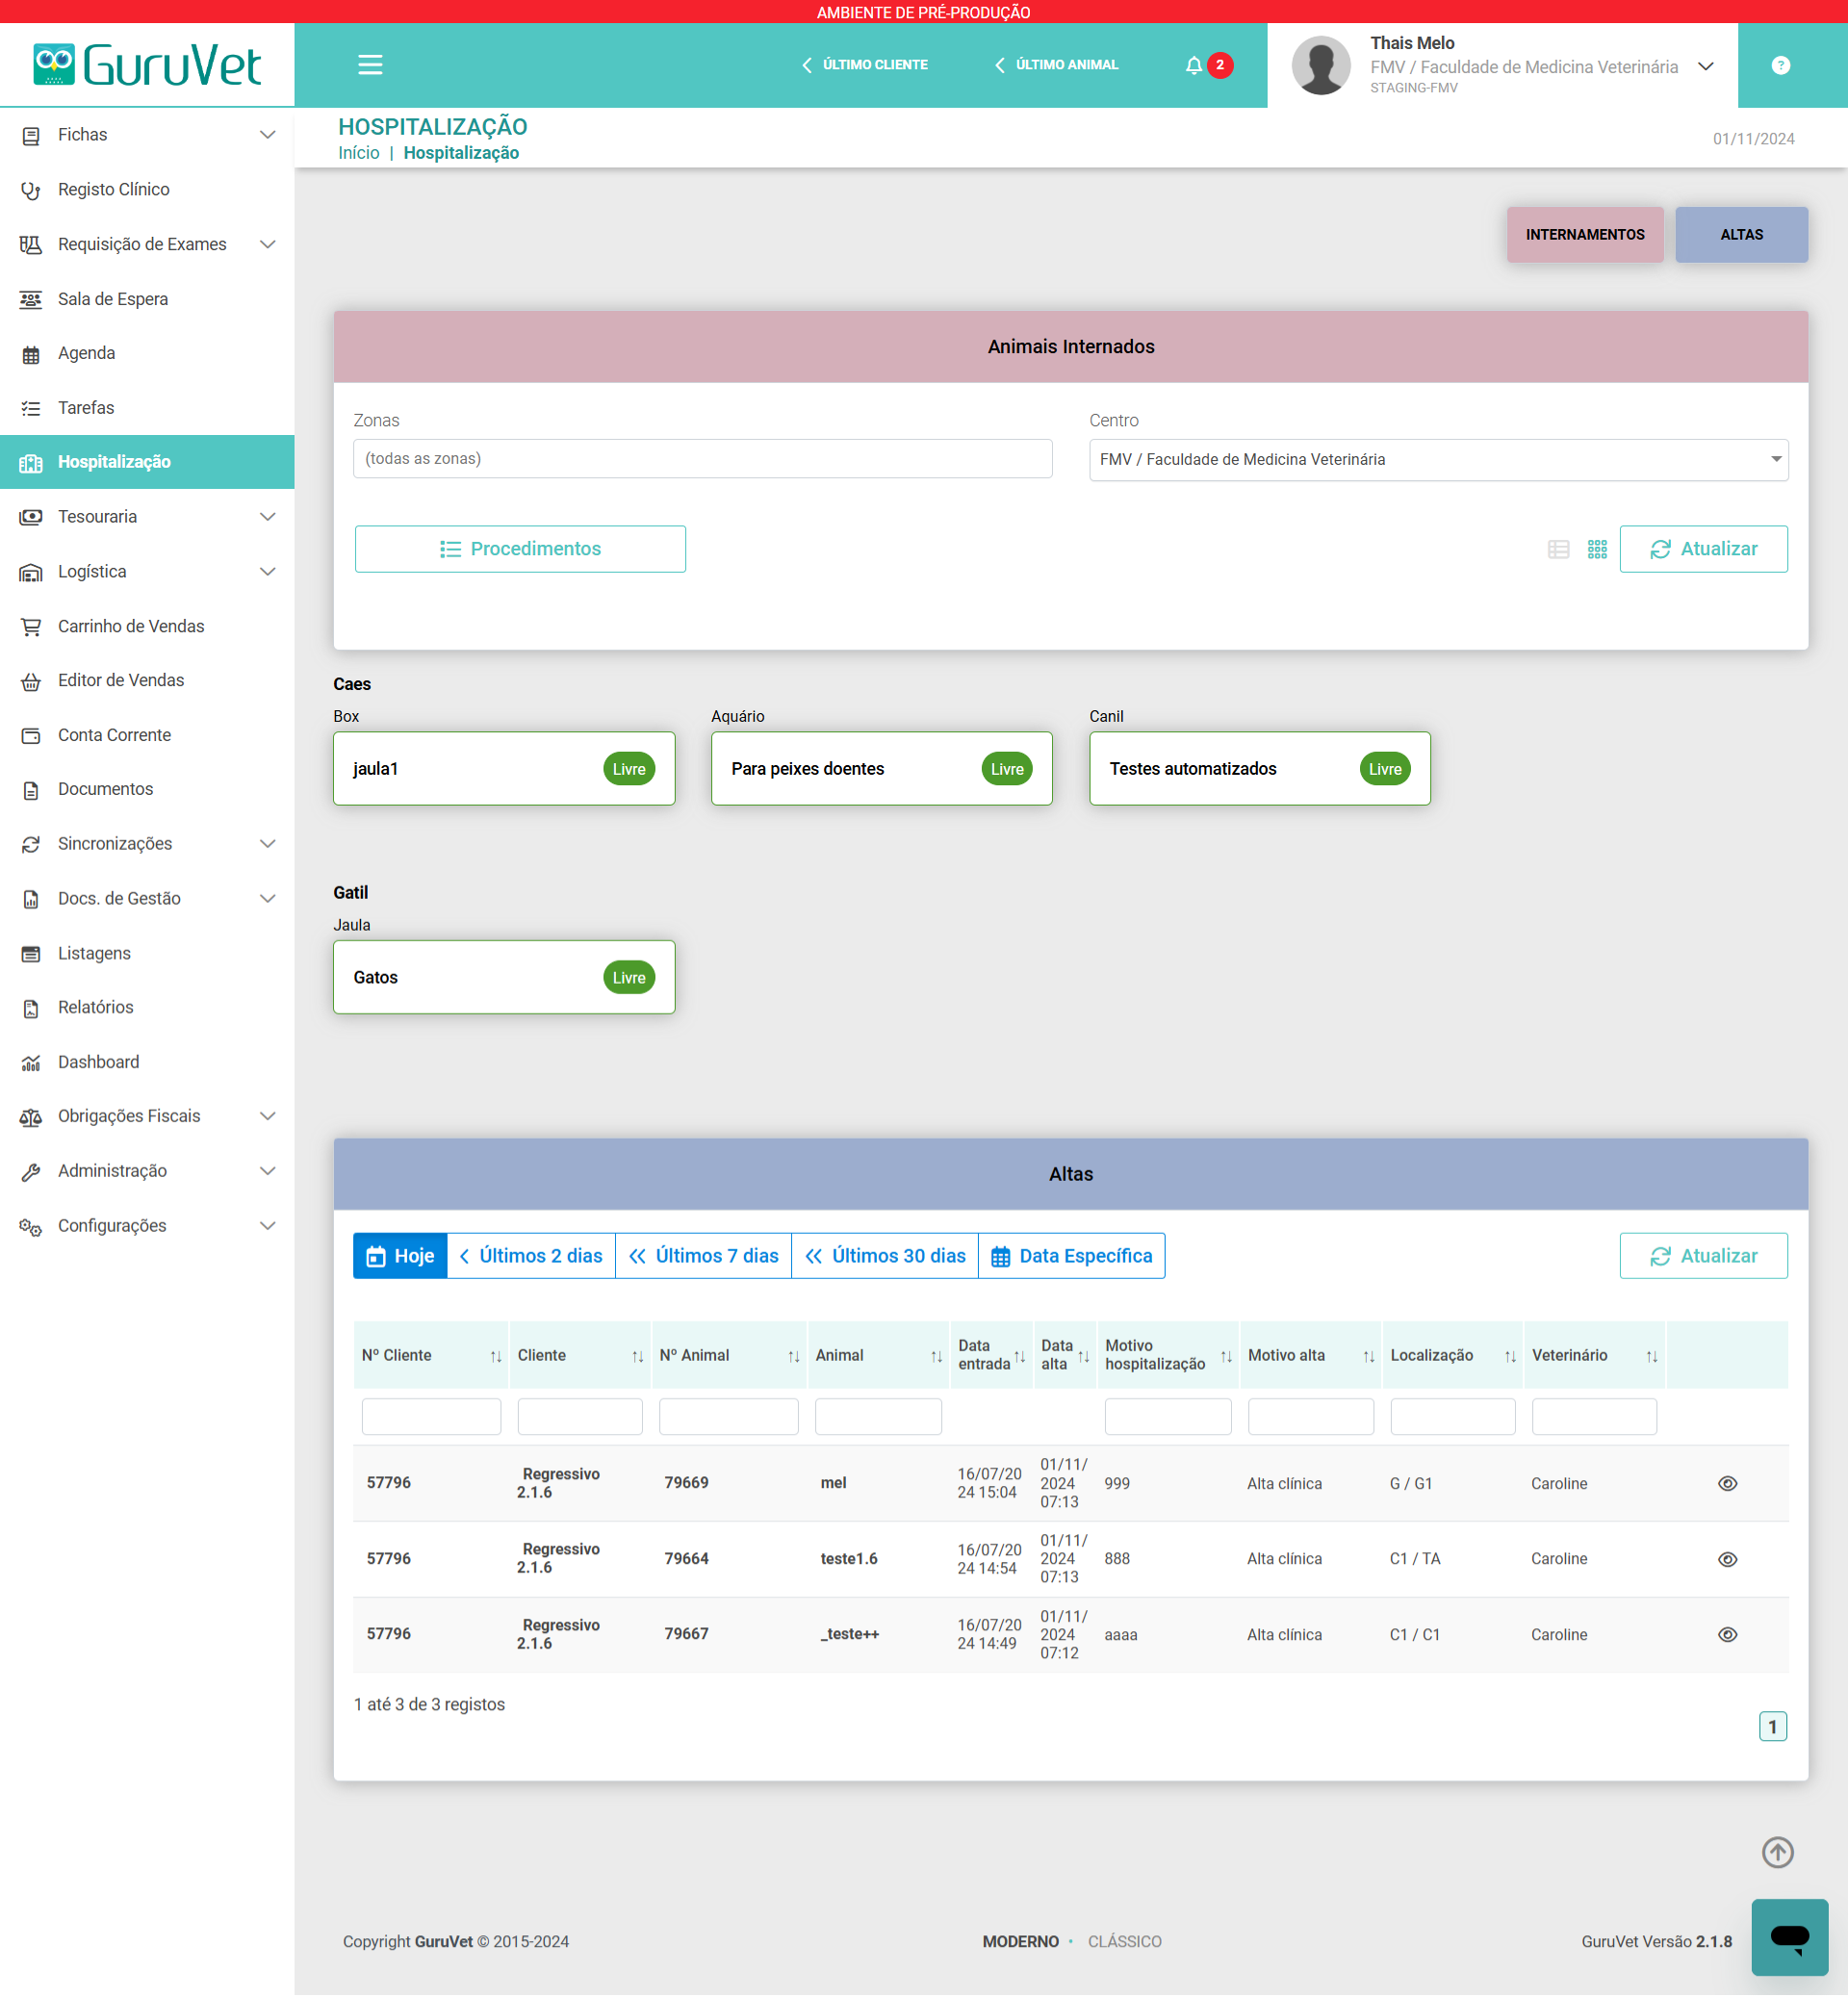

Disponha de todos os recursos necessários para uma gestão eficaz da sua clínica ou centro veterinário, num único software.

Aceda com facilidade ao histórico médico dos pacientes, bem como aos resultados de exames clínicos e de imagem.

PRODUTO

GuruVet - Software de Gestão para Clínicas e Centros Veterinários

O GuruVet é um sistema para clínicas veterinárias desenvolvido para ser o mais completo, intuitivo e fácil de utilizar possível, de forma a apoiar o veterinário e a sua equipa. Para criar o GuruVet, reunimos especialistas de várias áreas (administrativa, jurídica, contabilística, veterinária e tecnológica) para estudar o funcionamento dos centros veterinários e desenhar os processos de acordo com as boas práticas de gestão.